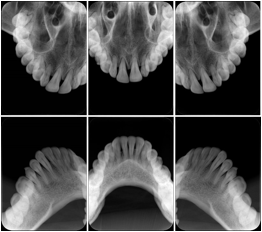

Intra-oral radiography typically involves acquisition of multiple images of various parts of the dentition. Many digital radiographic systems offer customized templates that are used for displaying the images in a study on the screen. These templates may also be referred to as mounts or view sets. The Structured Display Object represents a standard method of encoding and exchanging the layout and intended display of Structured Displays. A structured display object created in this manner could be stored with a study and exchanged with images to allow for complete reproduction of the original exam.

1. A patient visits a General Dentist where a Full Mouth Series Exam with 18 images is acquired. The dentist observes severe bone loss and refers the patient to a Periodontist. The 18 images from the Full Mouth Series along with a Structured Display are copied to a DICOM Interchange CD and sent with the patient to see the specialist. The Periodontist uses the CD to open the exam in his Dental Radiographic Software and consults via phone with the General Dentist. Both are able to observe the same exam showing the images on each user's display using the exact same layout.

Intra-oral Full Mouth Series Structured Display

Figure OO-1. Intra-oral Full Mouth Series Structured Display